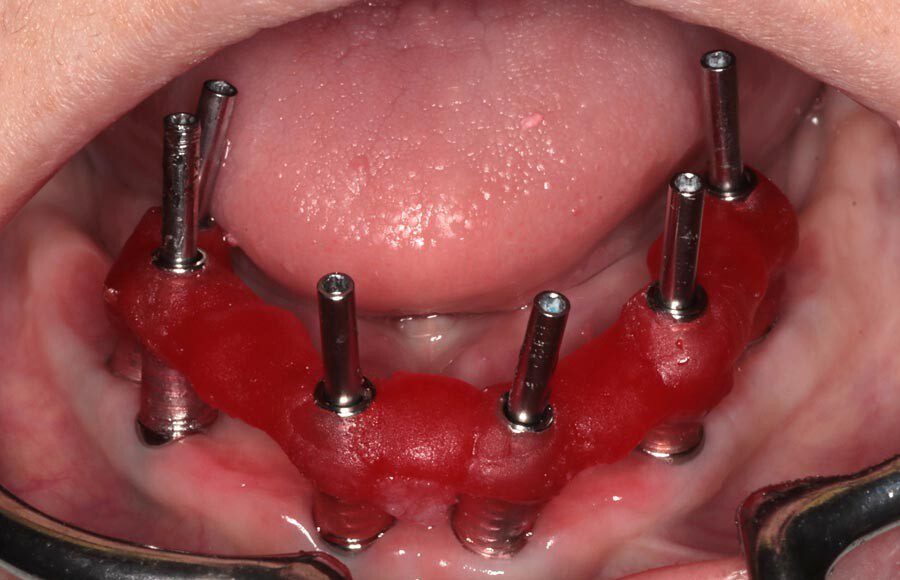

Splinted impressions are made for maximum accuracy at this stage. Records are completed and sent to our partner lab so they can start creating wax prototypes for us to test.